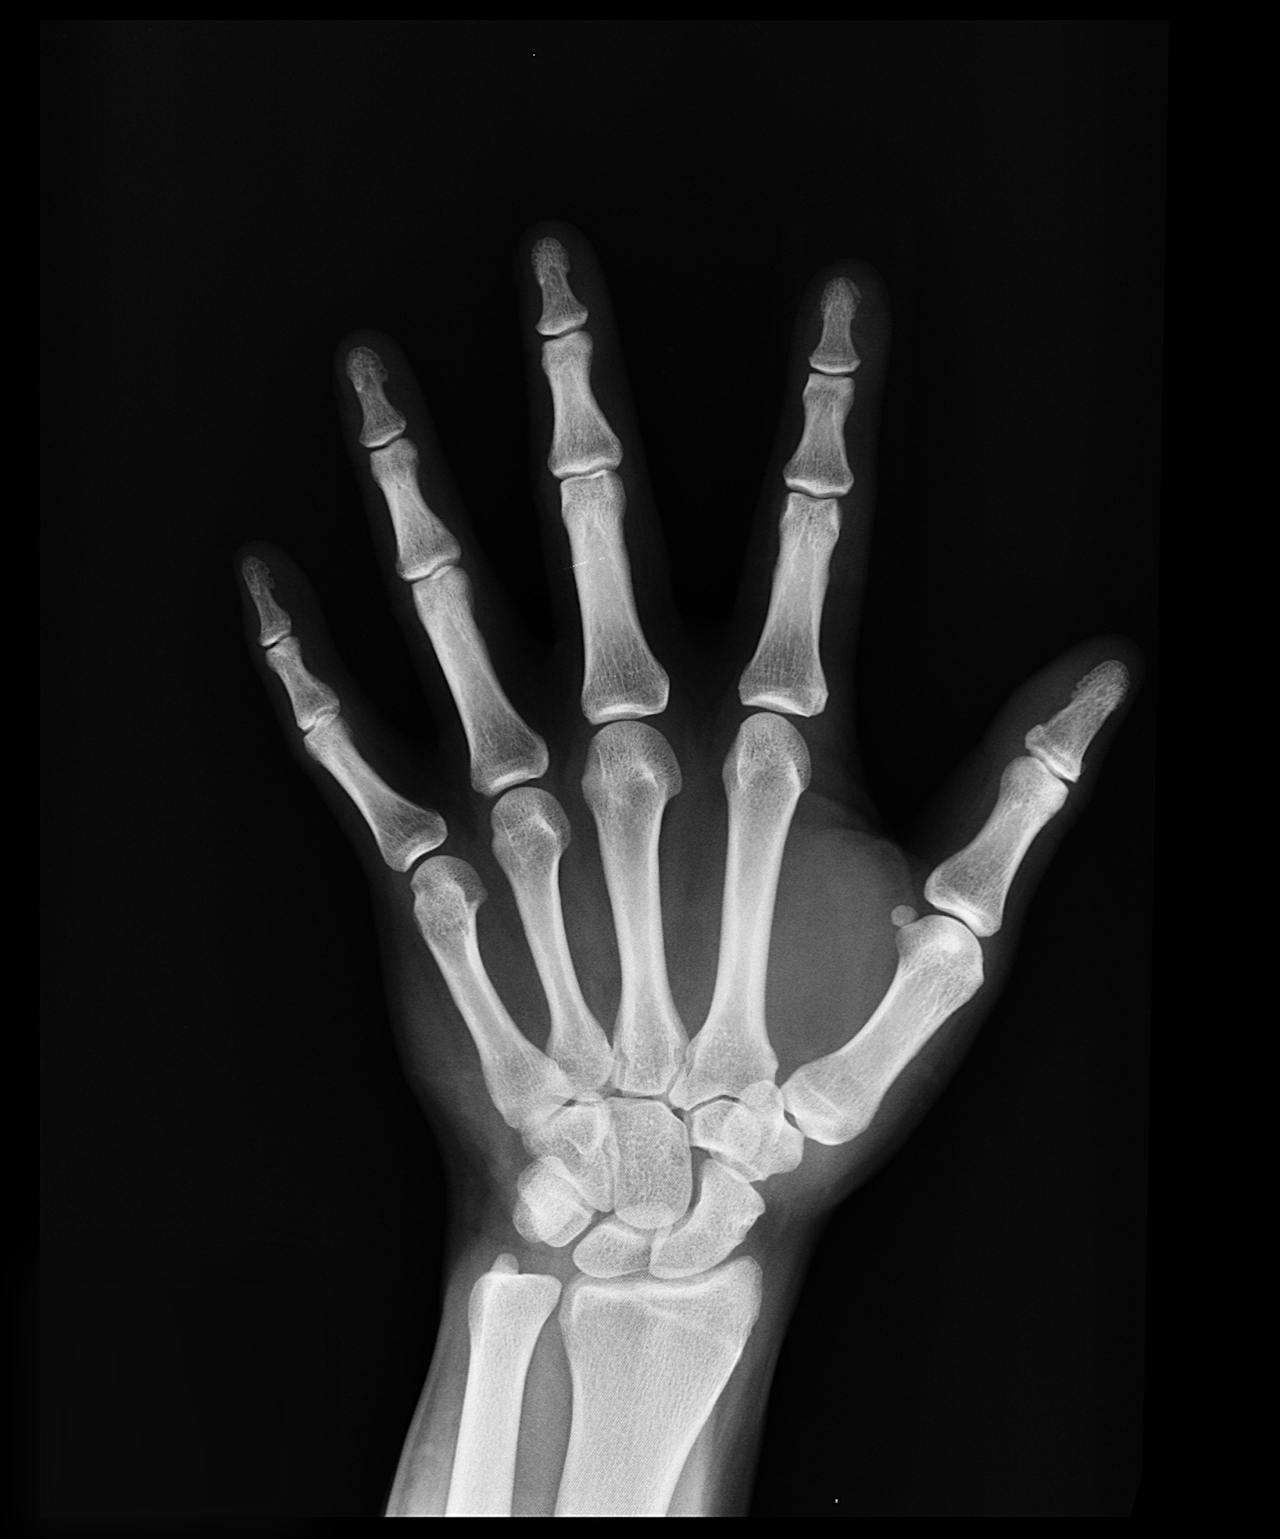

Metacarpals 掌骨

The metacarpals are five long bones in the middle part of your hand.

They connect the wrist bones to your fingers, making your hand strong and flexible.

Each metacarpal supports one finger and helps it move when you pick up or hold things.

These bones are covered by muscles and skin, so you cannot see them from the outside.